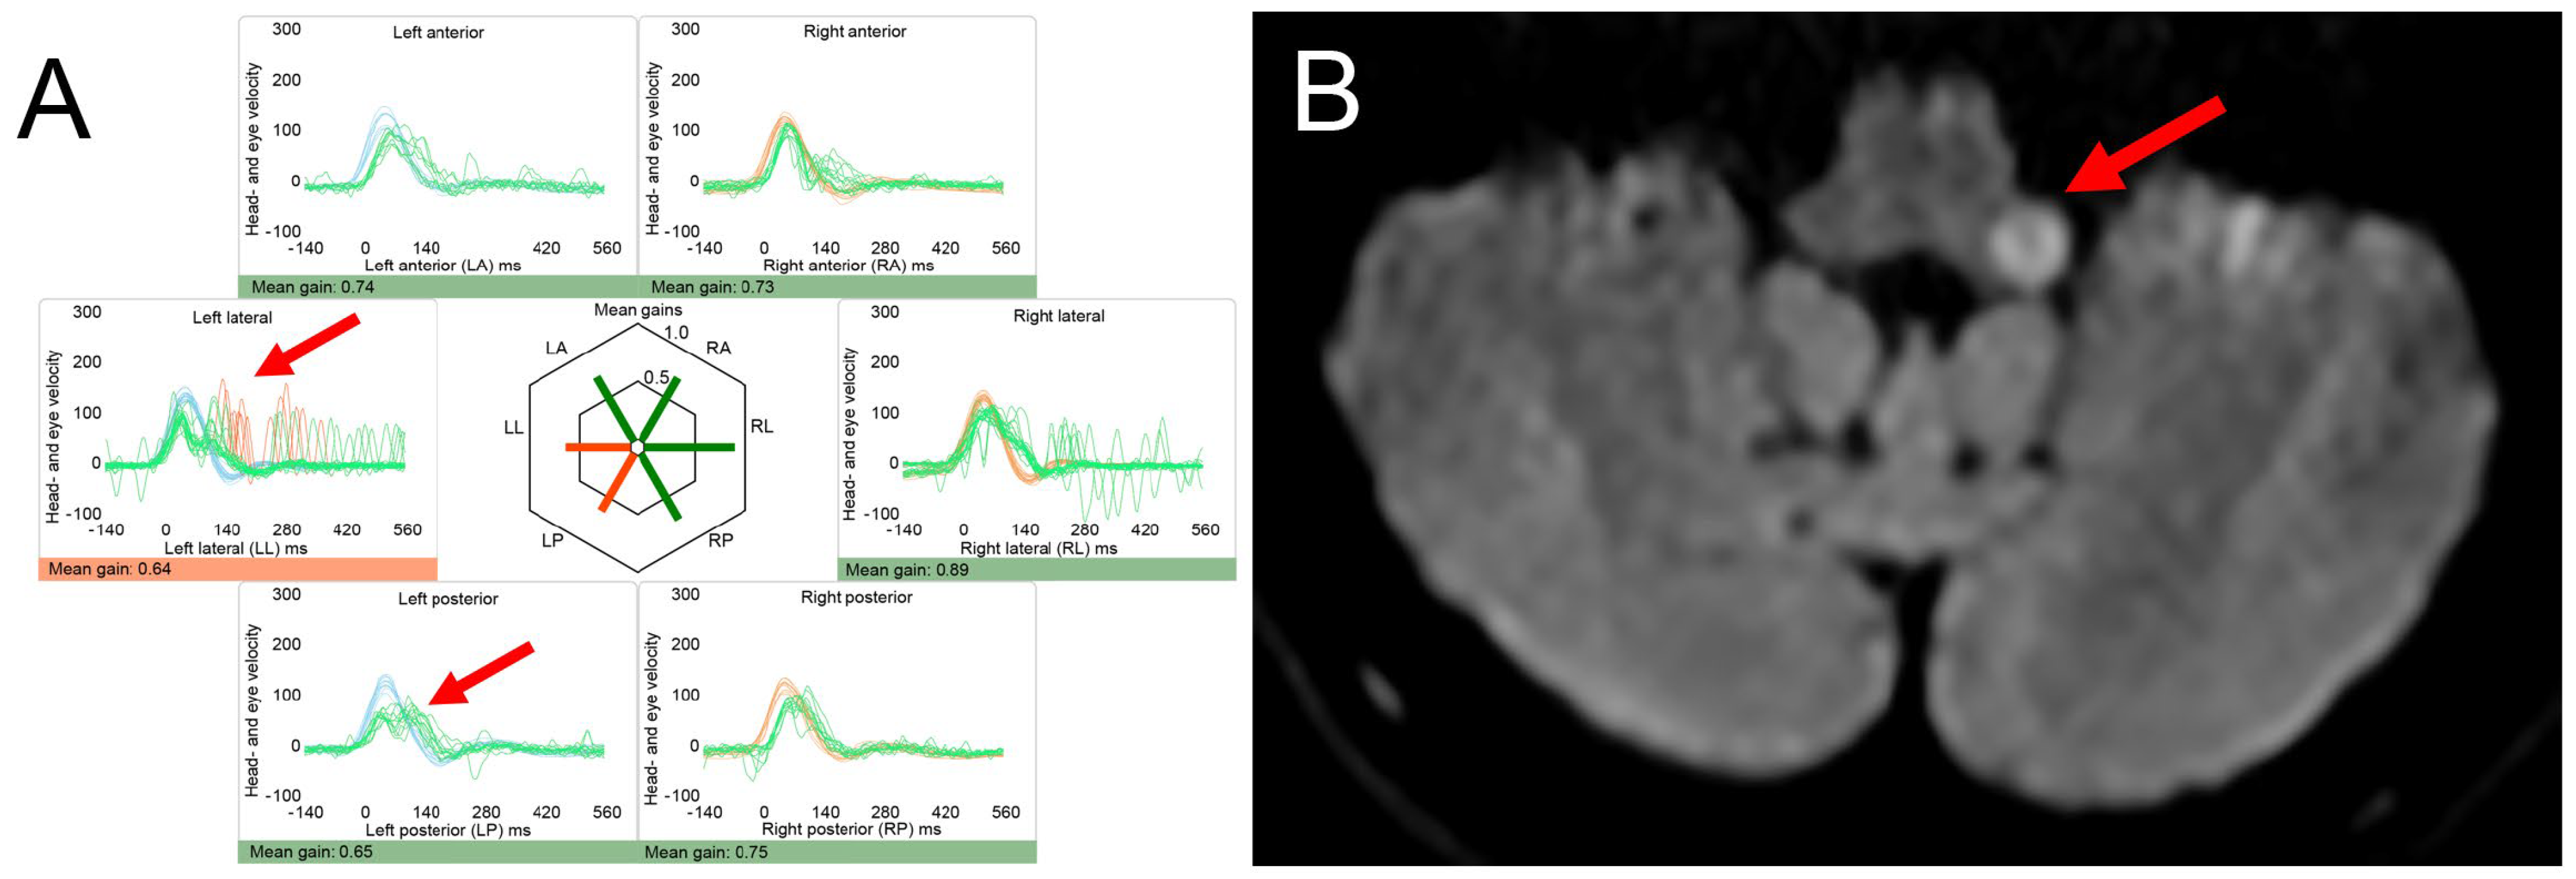

4.2. Posterior Fossa Tumors and (Other) Causes of Increased Intracranial Pressure